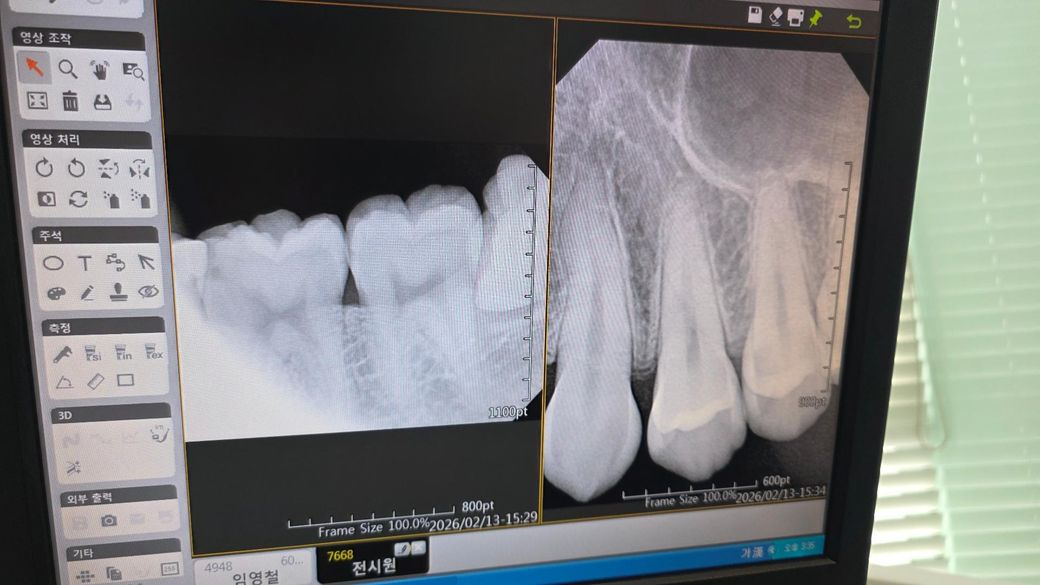

위에쪽 소구치가 신경치료를 해야할정도로 심하다는데 평생 통증도 없었고 아픈쪽은 아래쪽 사랑니쪽 치아인데 갑자기 통증도없는 위쪽을 신경치료하자해서 일단 검진만 받고 나왔는데 진짜 충치가 많이 심한가요? 보는법을 모르겠네요

• 1번 째 사진

치근단사진(작은 사진)에서 위 작은어금니의 치근단에 약한 염증 반응이 보이고, 충치로 의심되는 인접면 부위 양상이 있긴 합니다 다만, 좀 더 명확히 보려면 다른 각도로도 찍어보고 여러 임상테스트도 해봐야 할 것 같습니다